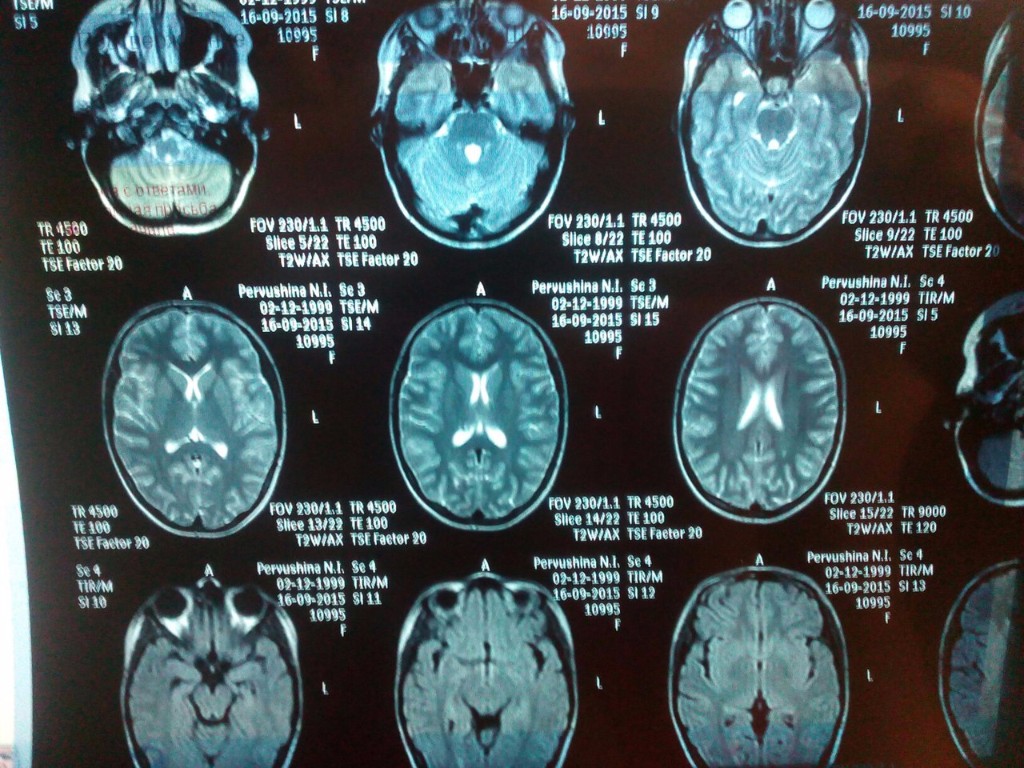

Медицинская диагностика: КТ и МРТ головного мозга